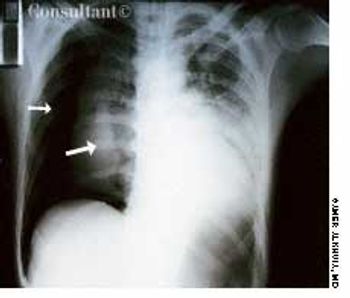

A 35-year-old man, a smoker, had right pleuritic pain, productive cough, and fever for 3 days. His pulse rate was 107 beats per minute; respiratory rate, 14 breaths per minute; blood pressure, 136/80 mm Hg; and temperature, 37.7°C (99.9°F). There were signs of right upper lobe consolidation. Laboratory studies showed hyponatremia. Chest films showed a homogeneous density in the right upper lobe.